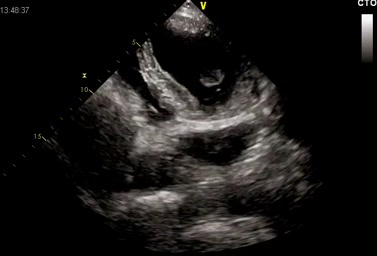

Asse lungo apicale. Appare evidente il malposizionamento (troppo in basso) della TAVI.